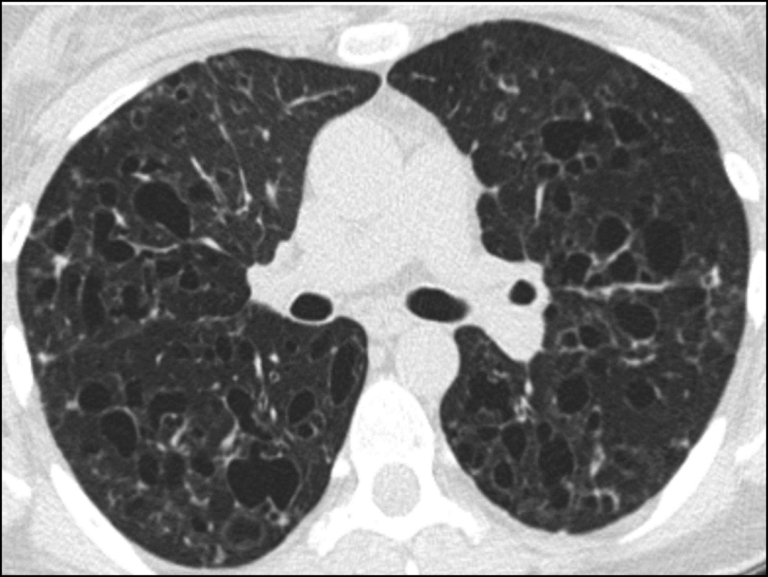

Radiology case Lung fibrosis, HRCT What Is Hrct Chest X Ray    hrct provides superior evaluation of lung abnormalities. This permits imaging of the fine structure of the lung.  chest radiography could provide a confident diagnosis in only 23 percent of cases, and those confident diagnoses proved correct. Subpleural honeycombing (red arrow), traction.   langerhans cell histiocytosis. More than 100 entities manifest as diffuse lung. The hrct shows focal bronchiectasis. What Is Hrct Chest X Ray.